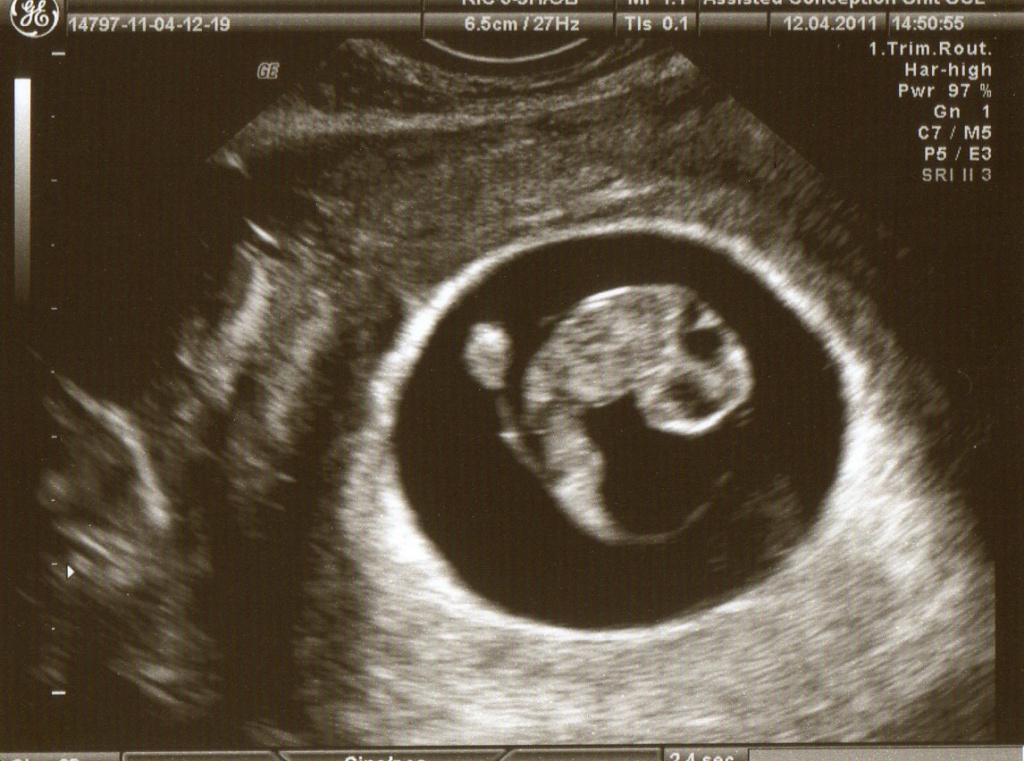

Восьмая неделя беременности: что происходит с вашим малышом? Ваш ребенок развивается с невероятной скоростью. Теперь он уже не размером с чернику, а с малиной. Однако определить точные размеры малыша все еще сложно. Хотя ультразвуковое исследование на восьмой неделе беременности может показать, что длина ребенка составляет около 20 миллиметров, это не означает, что он растет только в высоту. Рост может происходить в руках, ногах, спине и других частях этого крошечного организма, что предвещает значительные изменения в ближайшие месяцы. УЗИ на восьмой неделе беременности не всегда является обязательным, но иногда может быть рекомендовано врачом.

Ниже представлены фотографии УЗИ на 8 неделе беременности:

Ниже представлены фотографии УЗИ, показывающие размер плода на 8 неделе беременности:

Ниже представлены фотографии плода на восьмой неделе беременности: